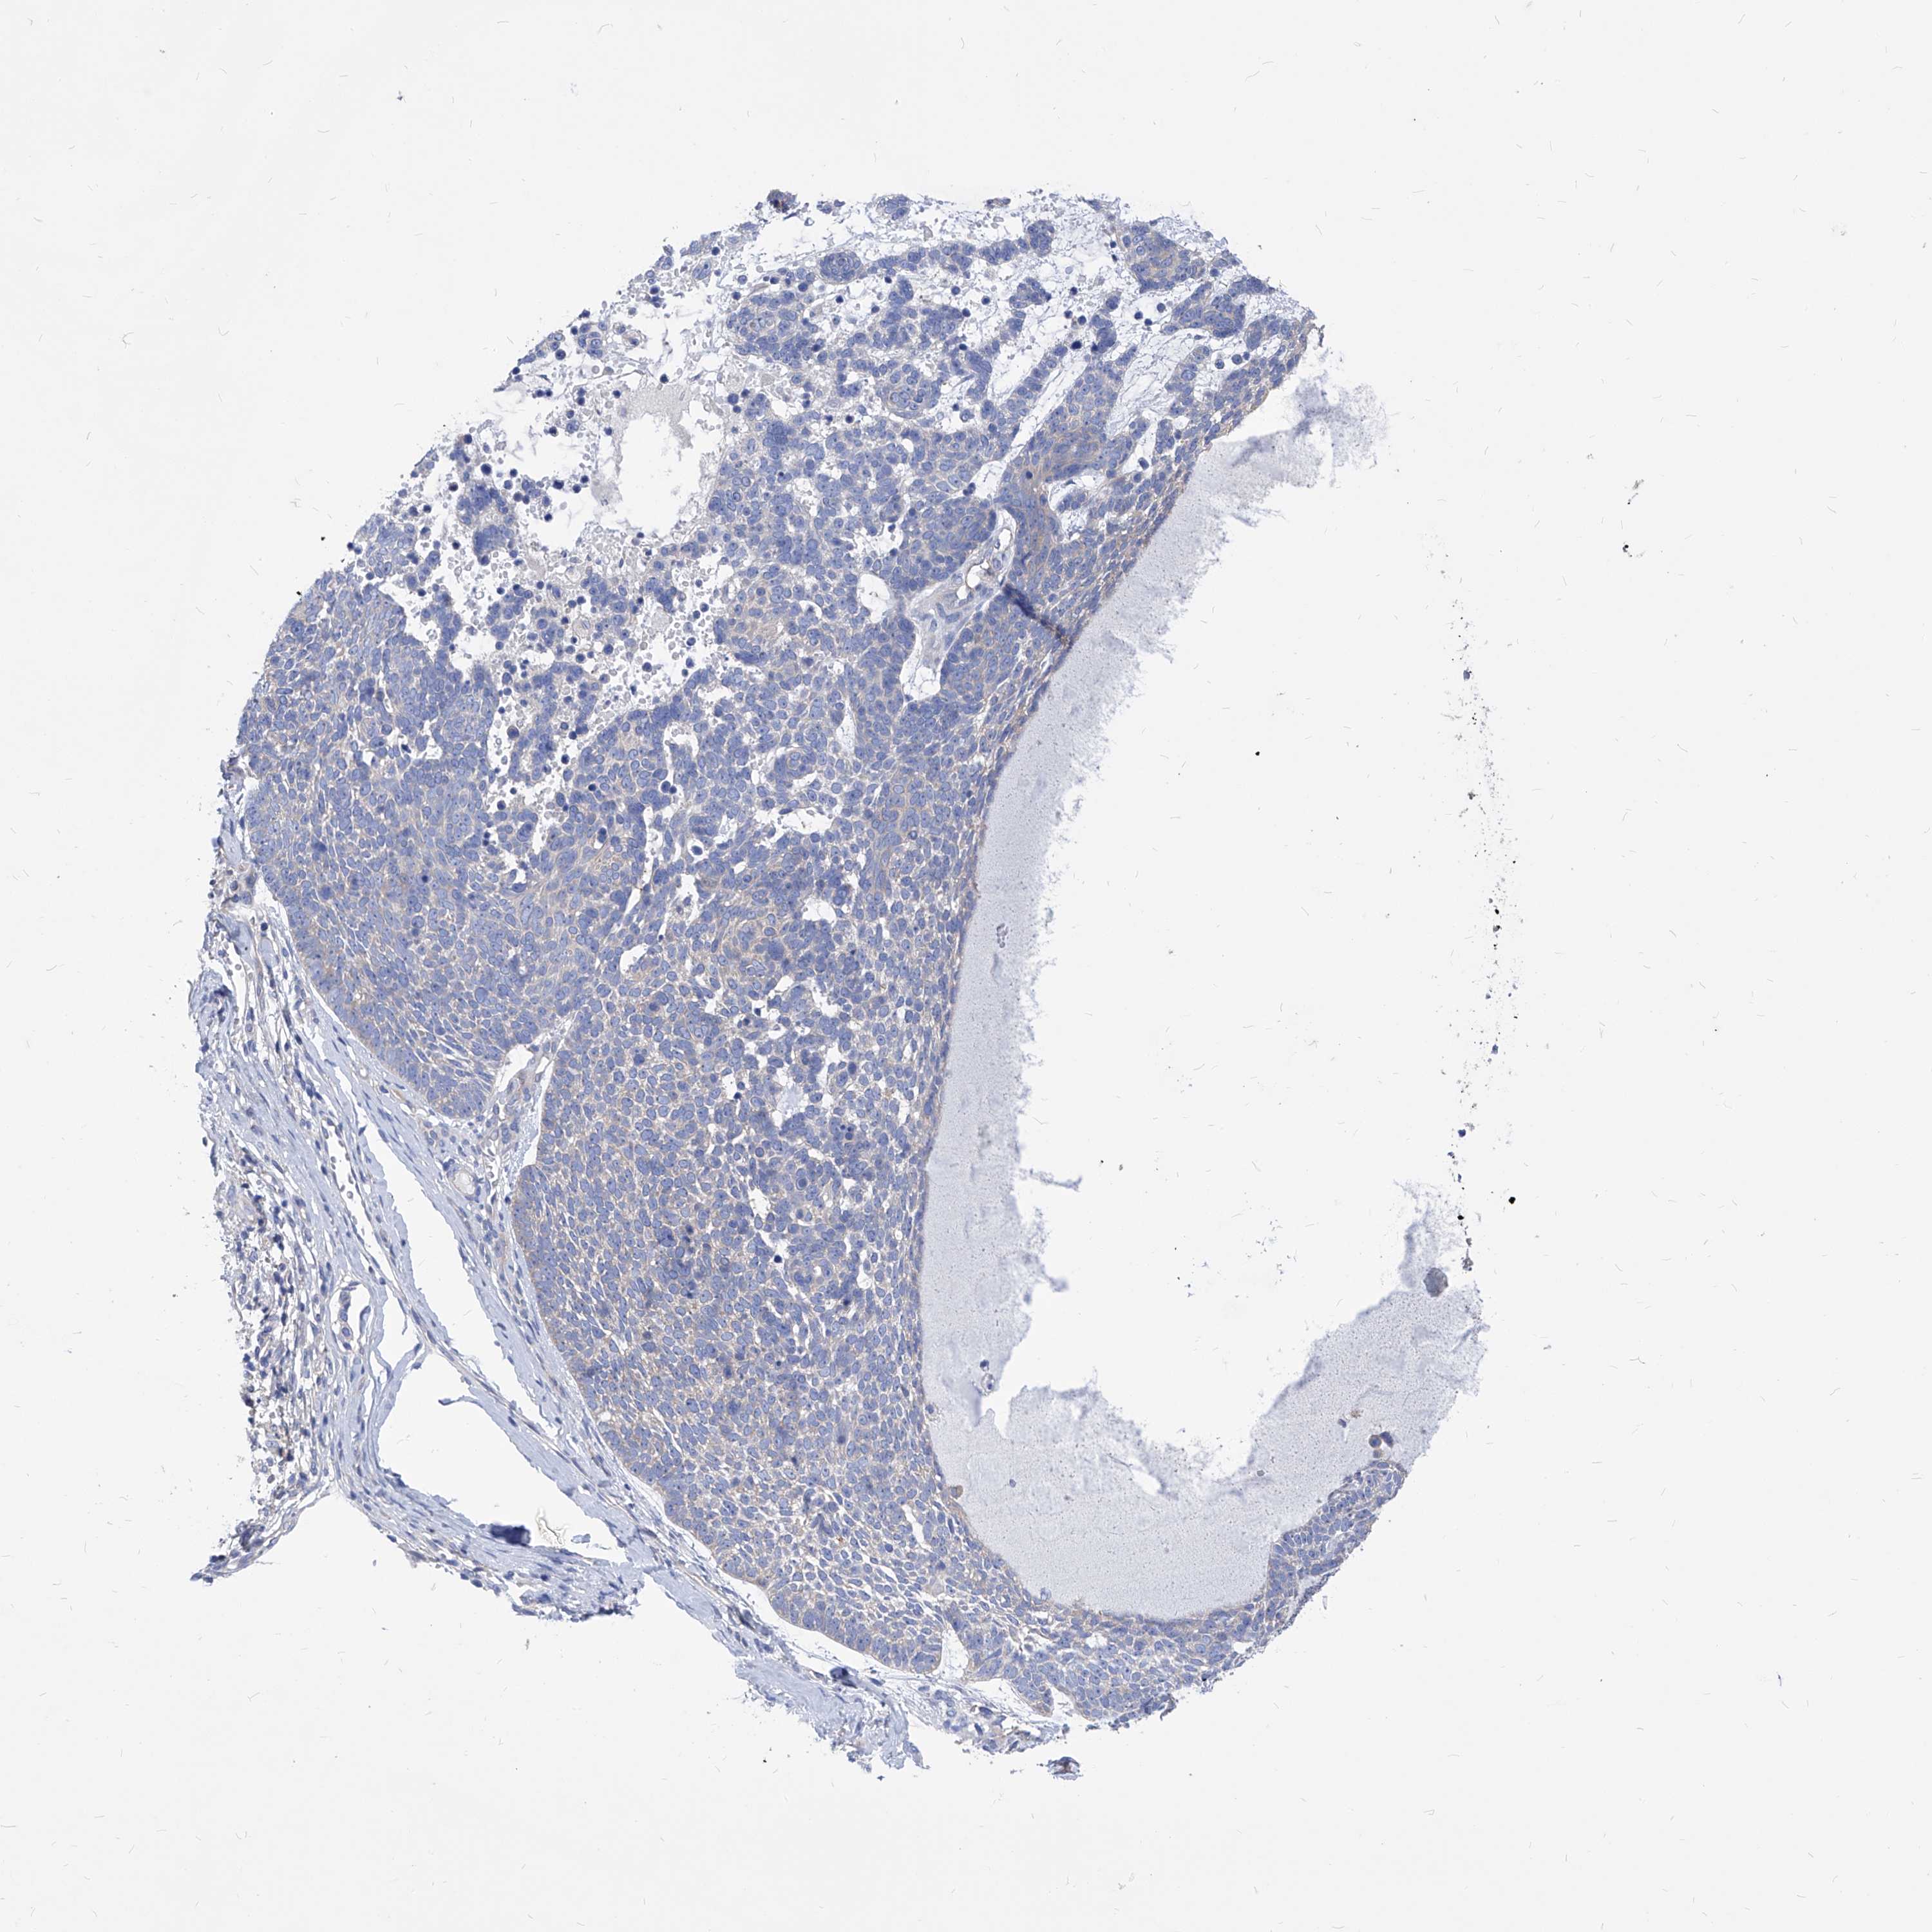

CANCER SKIN CANCER Show tissue menu

Basal cell and squamous cell cancer

SKIN CANCER - Protein expressioni

A mouse-over function shows sample information and annotation data. Click on an image to view it in a full screen mode. Samples can be filtered based on level of antibody staining by selecting one or several of the following categories: high, medium, low and not detected. The assay and annotation is described here.

Each image is clickable and will lead to virtual microscopy that enables deeper exploration of all samples and also displays staining intensity scores, fraction scores and subcellular localization as well as patient and tissue information for each sample.

Squamous cell carcinoma, NOS